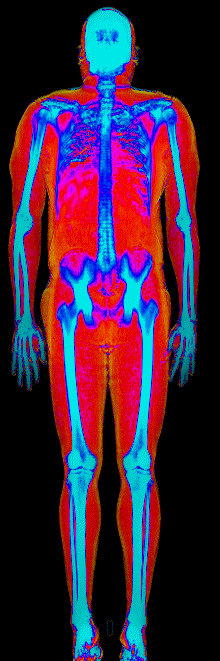

What Fat Loss Looks Like on a DEXA Scan

Red = muscle, gold = fat, blue = bone.

Lost 26.0 lb of fat · 187 → 150 lb · Age 44

Lost 25.4 lb of fat, gained 3.7 lb lean · 201 → 180 lb · Age 33

Lost 24.9 lb of fat, gained 12.0 lb lean · 183 → 170 lb · Age 37